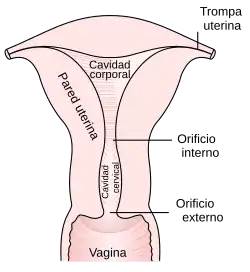

El cáncer de cérvix, carcinoma de cérvix, cáncer de cuello de útero o cáncer de cuello uterino incluye las neoplasias malignas que se desarrollan en la porción fibromuscular inferior del útero que se proyecta dentro de la vagina.

El cérvix uterino presenta lesiones asintomáticas mucho antes de la aparición del cáncer. Reciben el nombre de neoplasia cervical intraepitelial (CIN, por sus siglas en inglés). Estas lesiones son las precursoras del cáncer. Consisten en la desorganización o displasia del epitelio exocervical. Con los años, evolucionan hasta transformarse en carcinoma, aunque también pueden regresar espontáneamente. Estas alteraciones precursoras solo se detectan mediante la citología, la colposcopia y la biopsia y observación al microscopio. Según el grado de evolución que presenten al observarlas con el microscopio se clasifican en tres grados:

Además del test Papanicolaou, el médico realizará otras pruebas para poder establecer más claramente el diagnóstico, como la colposcopia, (visualización del cuello del útero durante la inspección ginecológica con la ayuda de un espéculo) para examinar las células cervicales más detalladamente con aparatos de aumento especiales. Se pueden detectar lesiones premalignas y malignas en estadios tempranos, donde los pacientes se curan con terapias como la conización. La conización es una forma más extensiva de biopsia en la cual se extrae una cuña del cérvix. Puede ser indicado realizar una biopsia para extraer una muestra que será estudiada con microscopio. Durante un legrado uterino se toman muestras del canal cervical y del útero y así hacer exámenes al microscopio.